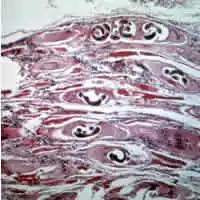

| Trichinella larvae in pressed bear meat, partially digested with pepsin. The classic coil shape is visible. | |